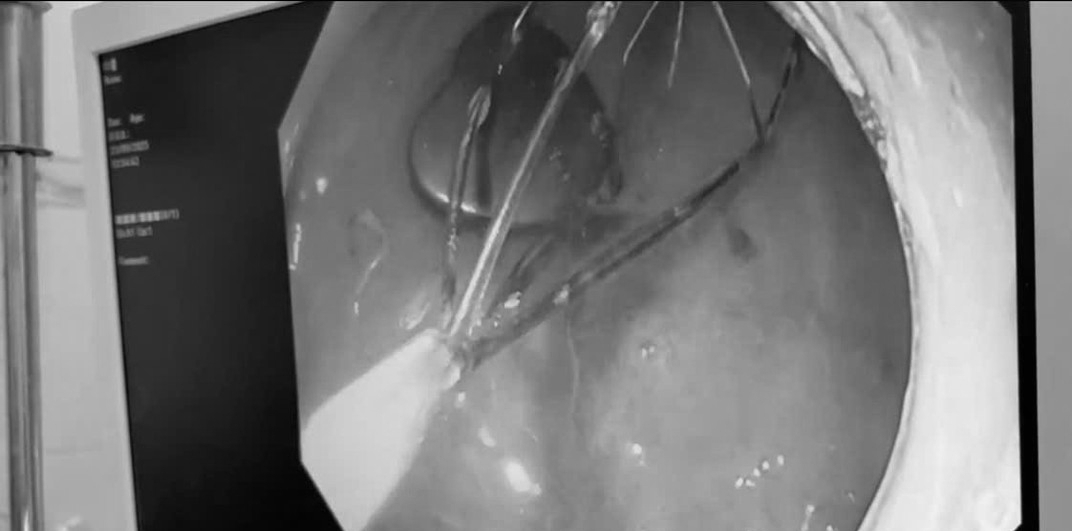

Nội soi lấy nam châm hình trái tim trong dạ dày bệnh nhi. Ảnh BVCC/Tri thức & Cuộc sống

Ngay lập tức, bệnh nhi được chuyển đến Khoa Nội soi. Ê-kíp bác sĩ tiến hành nội soi gây mê, sử dụng dụng cụ chuyên dụng để gắp dị vật. Sau một khoảng thời gian ngắn, cục nam châm đã được lấy ra an toàn. Kiểm tra đường tiêu hóa không ghi nhận tổn thương, bé tỉnh táo và được xuất viện trong ngày.